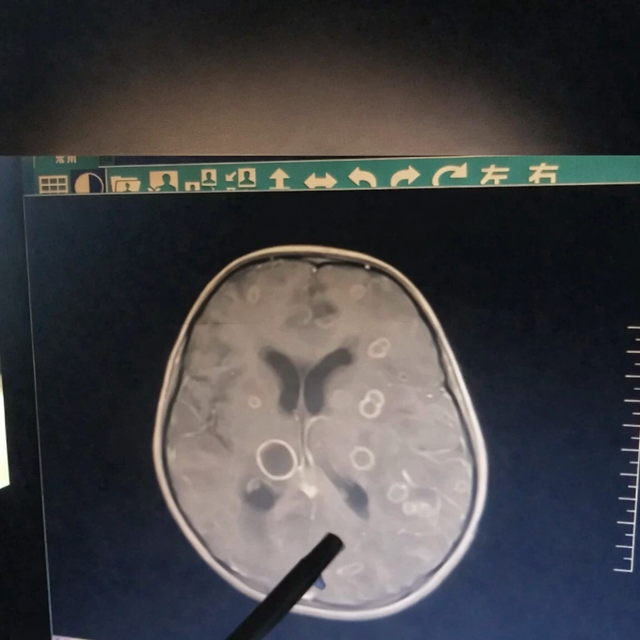

Kết quả kiểm tra khiến các bác sĩ không khỏi bàng hoàng: trong não của đứa trẻ xuất hiện hơn chục ổ tổn thương lớn nhỏ, giống như bị “gặm nhấm” từng mảng.

Mới đây, một bé gái 6 tuổi ở Trung Quốc bị sốt liên tục suốt 17 ngày, dần rơi vào tình trạng lơ mơ, rối loạn ý thức và được chuyển gấp tới Bệnh viện trực thuộc Đại học Trịnh Châu (Trung Quốc). Kết quả kiểm tra khiến các bác sĩ không khỏi bàng hoàng: trong não của đứa trẻ xuất hiện hơn chục ổ tổn thương lớn nhỏ, giống như bị “gặm nhấm” từng mảng.

Bác sĩ cho biết, nếu đến muộn thêm vài ngày, tổn thương có thể lan rộng đến mức đe dọa trực tiếp tính mạng.

Sau khi chọc hút dịch trong các ổ tổn thương để xét nghiệm, “hung thủ” cuối cùng cũng lộ diện: nấm Aspergillus fumigatus, hay còn gọi là nấm khói.